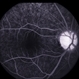

- Behcet's Disease

- Korean male with unilateral vasculitis / mouth ulcers.